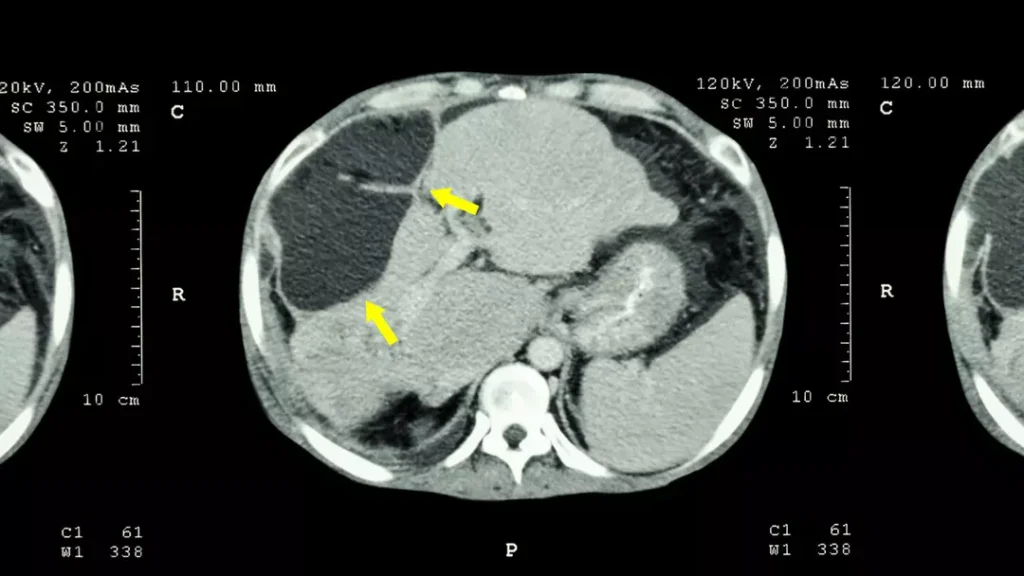

Kadınlara oranla erkeklerde beyin kanamasına daha sık rastlandığını belirten Doç. Dr. Çakın, “Anevrizmatik kanamalar beyindeki atardamarların baloncuklaşması sonucu oluşan beyin kanamaları olarak biliniyor. Özellikle sonbahar ve ilkbaharın başlarında bu kanamaların yüzde 10 arttığı görüldü. Beyinde bulunan atardamarlar üzerinde sigaranın da etkisiyle baloncuk oluştuğu görüldü” ifadelerini kullandı.

Genetik hastalıkların beyin kanamasında etkili olabileceğini söyleyen Doç. Dr. Hakan Çakın, “Hipertansiyon, sigara ve ileri yaşın etkisiyle oluşan bu baloncuklar, mevsim döngülerinin olduğu zamanlarda daha çabuk yaşama eğilimi göstererek beyin kanamasına sebep oluyor. Çocuklarda daha nadir görülüyor. Genetik olarak görülen anevrizmalar özellikle Japonya ve Finlandiya’da çocuk yaşlarda da sıklıkla görülebiliyor ama ülkemizde o kadar sık değil. Belli yaşın üzerinde, özellikle 30-50 yaştan sonra hipertansiyon ve sigaranın bu konuda çok etkisi var. Genç yaşlarda görülenlerin de at nalı böbrek, diyalize giren hastalar ya da tansiyon sorunları ve genetik hastalıklar etkili olabiliyor” dedi.